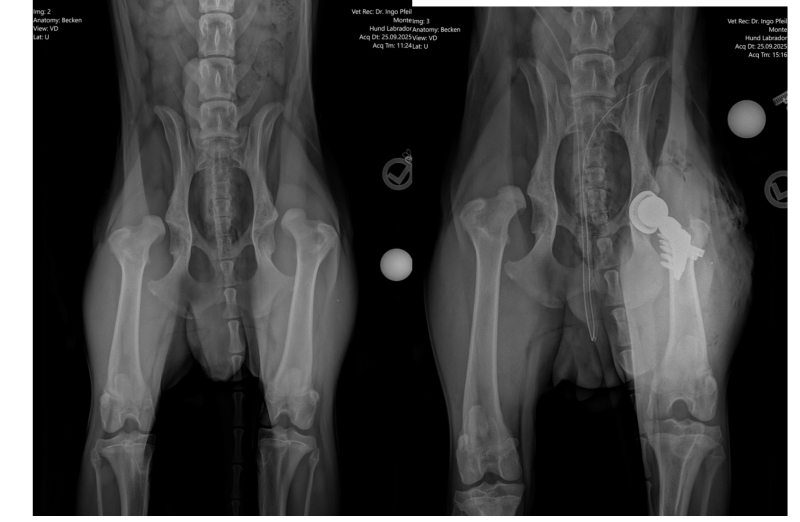

Unser Jungspund hat in diesem Jahr das teuerste Weihnachtsgeschenk bekommen, nämlich sein zweites künstliches Hüftgelenk. Nachdem Dr. Pfeil die Kontrollröntgenbilder für so gut eingeschätzt hat, dass nunmehr bereits die andere stark deformierte Hüfte ersetzt werden kann, folgte eine Woche später schon die Operation in Dresden.

Leider stellte Dr. Pfeil in der Tierklinik fest, dass sich die Hüften innerhalb der letzten vier Wochen derart verschlechtert hatten, dass eine DARthroplastik nicht angewandt werden konnte und nunmehr beide Hüften durch künstliche Gelenke ersetzt werden müssen. Als erste OP wurde nun das linke Hüftgelenk ersetzt. Alles ist gut gelaufen und das Entscheidende ist nun der Heilungsprozess, was bei so einem Wirbelwind eine große Herausforderung darstellt.

Hoffen wir mal, dass alles gut verläuft und bald schon die 2. Operation vorgenommen werden kann!